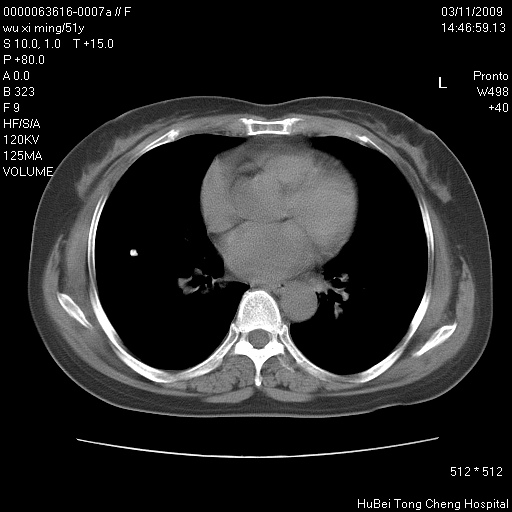

患者 女,51岁。因“胆囊炎,胆囊结石”,行常规术前胸部x线检查发现:右上肺结节病灶,建议行进一步检查。患者无咳嗽、咳痰及咯血等呼吸道症状,近期出现背部疼痛不适。

胸部ct轴位平扫(层厚10mm,螺距1.5,重建间隔10mm;部分层面:层厚3mm,螺距1.0,重建间隔3mm),图像如下: